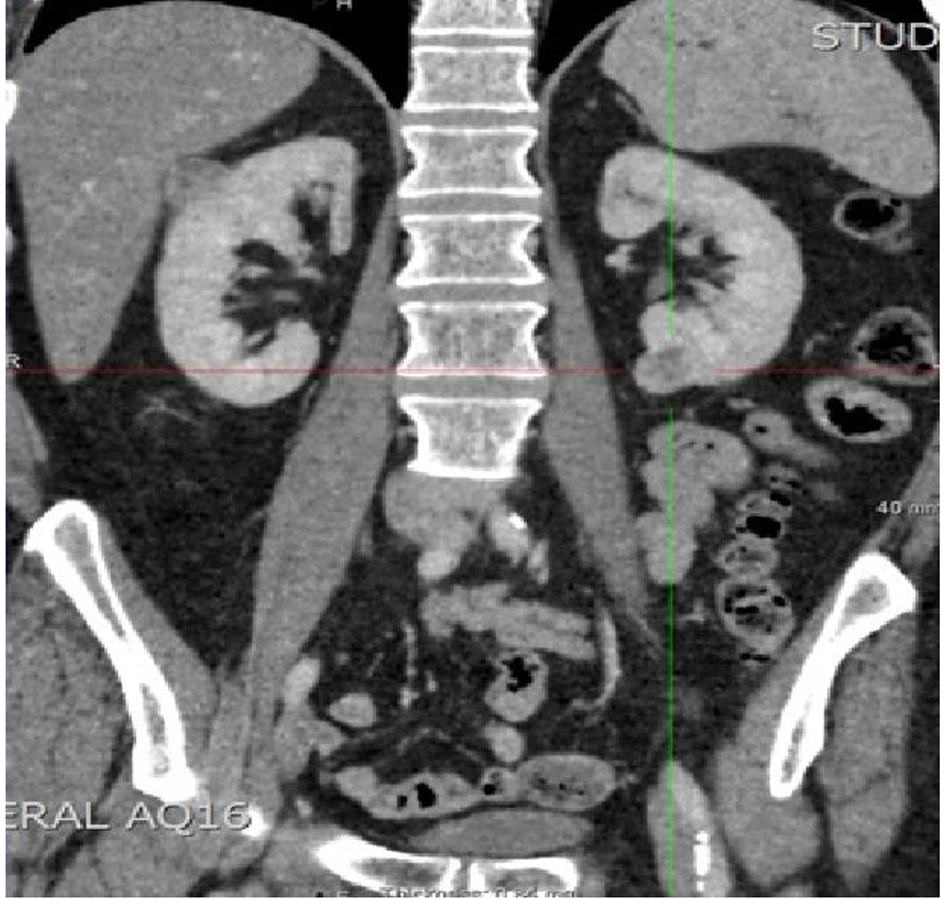

We present the rare case of a 58-year-old Caucasian male who developed bilateral metastatic renal hemangiopericytomas 14 years after undergoing resection of the primary from the posterior cranial fossa. During this period, a small cranial recurrence was further resected and a small solitary lung metastasis confirmed on biopsy was identified. It was during surveillance for the lung lesion that a new 2.4 cm right upper pole and a 2 cm left lower pole renal masses were detected on CT scanning which raised suspicion of secondary metastases in view of the history (Fig. 1). There was an initial decision to keep these lesions under surveillance because of their size but in view of the patient’s symptoms and heightened anxiety, a left partial nephrectomy was undertaken in the first instance with histology subsequently again confirming HPC (Fig. 2). At the present time, it remains the intention to keep both the lung and right renal lesions under surveillance until such time there are any concerns.

![]() Click for large image | Figure 1. CT showing bilateral renal masses. |